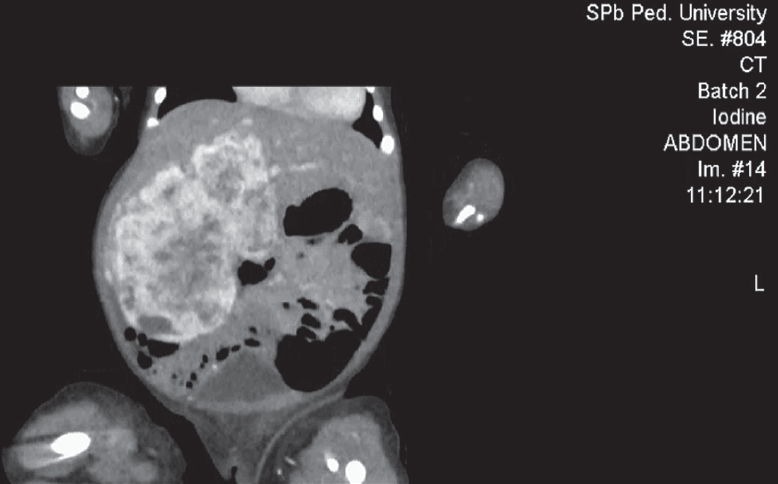

Проведено обследование: УЗИ органов брюшной полости — визуализируется объемное образование с кровотоком, занимающее всю правую долю печени. МСКТ брюшной полости с контрастным усилением — выявлено гигантское сосудистое образование печени срединного расположения (рис. 8).

Рис. 8. Аксиальные компьютерно-томографические снимки во все фазы контрастирования

Fig. 8. Axial CT images in all phases of contrast